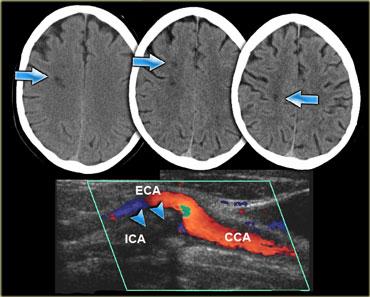

Bên trái là ba lát cắt CT liên tiếp của bệnh nhân tắc động mạch cảnh trong phải.

Tình trạng giảm tưới máu bán cầu phải dẫn đến nhiều ổ nhồi máu vùng ranh giới sâu.

Hình thái nhồi máu vùng ranh giới sâu này khá phổ biến và cần thôi thúc người đọc tiến hành khảo sát các động mạch cảnh.

Bên trái là hình ảnh của bệnh nhân có các ổ nhồi máu nhỏ ở bán cầu phải tại vùng ranh giới sâu (đầu mũi tên màu xanh lam) và tại vùng ranh giới vỏ não giữa lãnh thổ ĐM não giữa (MCA) và ĐM não sau (PCA) (mũi tên màu vàng).

Có bất thường tín hiệu tại động mạch cảnh phải (mũi tên màu đỏ) do hậu quả của tắc mạch.

Ở những bệnh nhân có các bất thường gợi ý nhồi máu vùng ranh giới, cần luôn khảo sát hình ảnh động mạch cảnh để tìm kiếm bất thường tín hiệu.